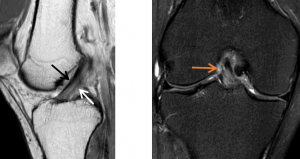

如图A所示,矢状面观察,正常的前交叉韧带(ACL),其特征是从胫骨平台向前延伸到股骨外侧髁的内侧的纤维是绷紧的、连续的、低信号强度的纤维,ACL的较前部分是前内侧(AM)束(黑色箭头),而较后部分是后外侧(PL)束(白色箭头)。

如图B所示,冠状面观察,可在髁间窝内观察到明显的前交叉韧带成像(橙色箭头)